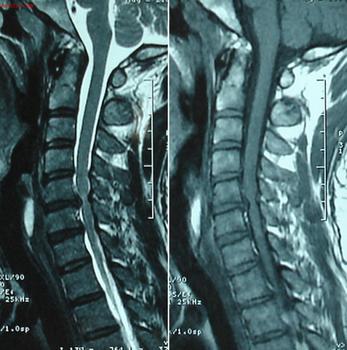

进行放射及实验室诊断:放射学的诊断是诊断强直性脊柱炎疾病的重点。因为凡是强直性脊柱炎都会出现骶髂关节炎,且骶髂关节是该病较早的受累 关节,所以那些怀疑患有强直性脊柱炎的人,应该拍摄骨盆的正位片。如果在X片上表现的不明显的话,就采取CT、磁共振等影像学的诊断来诊断强直性脊柱炎疾病。